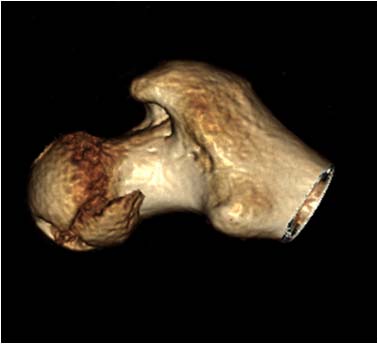

Через 12 дней выполнен остеосинтез головки 3-мя самокомпрессирующими винтами Герберта. Доступ Kocher-Langenbeck с флип-остеотомией большого вертела и задним хирургическим вывихом головки бедра. Интерпонирующий внутрисуставной фрагмент представлял собой лабрум с тонкой костной пластинкой от заднего края впадины. Фрагмент извлечен и фиксирован техникой spring-plate.

Обращал на себя внимание значительный дефект хряща головки бедра в нагружаемой зоне (как результат контакта головки с внутрисуставным фрагментом). Глубина повреждения хрящевого покрытия в центральной части дефекта достигает кости. Ничего не делали, расчитывая на замещение дефекта фиброзным хрящом. Промыли головку с впадиной, вправили вывих и ушились с активным дренажом.

Из литературы известно, что повреждения Pipkin IV, а особенно Pipkin III, нередко приводят к развитию тяжелого коксартроза с последующей заменой сустава. Возникают вполне резонные вопросы о целесообразности остеосинтеза в нашем частном случае, где есть дефект хряща в нагружаемой зоне. Что скажет сообщество? Есть ли смысл в первичном эндопротезировании, несмотря на еще молодой возраст? Есть ли надежные хирургические приемы по восстановлению хрящевого покрытия? На ум приходит что-то вроде микроперфораций, донорские хрящевые столбики и т.д. Есть ли резон?